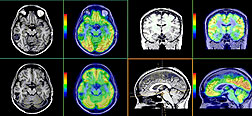

MRIの画像は、

表示の仕方で、

白や黒で映る画像や、

赤や緑などで映るカラフルな画像なんかもあります。

その赤や緑などで表示した画像のものも見せてもらいましたが、

けっこうハッキリときれいに映っていました。

その表示の画像だと、

異常がある箇所は色が出てこないみたいです。